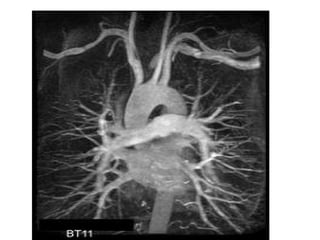

Surgery- coronary artery bypass graft (CABG)

They take a vein from somewhere in the bodylike the saphenous from the leg, or mammary

vein from the chest and bypass the artery with

the clot.